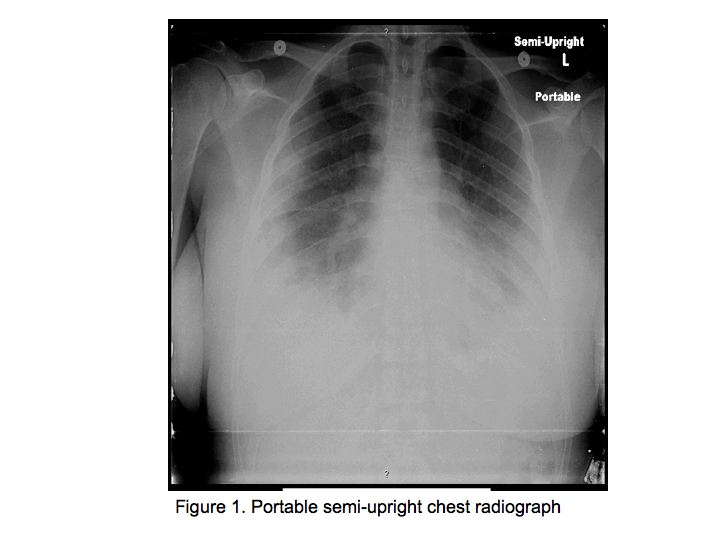

The patient was alert and oriented. Pulse was 110 beats per minute, blood pressure 100/73 mm Hg, respiratory rate 30 per minute, temperature 37.8 ºC, Oxygen saturation was 90% on room air. No cyanosis or clubbing was noted. Pupils were equal and reactive to light. Neck examination revealed no abnormality. Precordial examination revealed tachycardia, but no murmurs, rubs or gallops. Patient demonstrated a rapid, shallow breathing pattern, but was not using accessory respiratory muscles. On auscultation he had normal vesicular breath sounds bilaterally. Abdomen was soft, with normal bowel sounds. Skin examination revealed several pinpoint, needle-like marks on the chest, buttocks and thighs. No peripheral edema was noted. His joints were non-tender, not warm to touch and free of swelling or deformity. Neurologic examination was within normal limits.

The patient was admitted to the medical floor and was started empirically on antibiotics. Cultures were obtained and an HIV test was done. Bronchoscopy was planned the next day which revealed diffuse erythema and hemorrhage in both the bronchial trees as shown in Fig. 5.